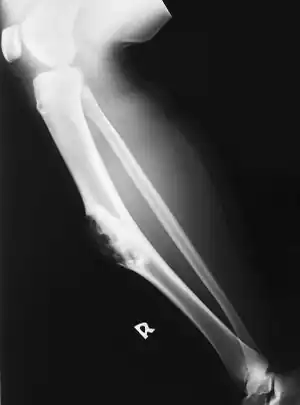

| Osteofibrous dysplasia of tibia (lower leg) | |

Osteofibrous dysplasia is a noncancerous bone tumor.[1] It most often affects the large long bone of the lower leg in young children.[2][3]

It is considered a fibrovascular defect. Campanacci described this condition in two leg bones, the tibia and fibula,[4] and coined the term.

Osteofibrous dysplasia most often presents as a localized firm painless swelling of the large long bone of the lower leg in young children.[2] The leg may appear bent and it is possible that a break in the bone can occur.[2][5]

It is rare, particularly over the age of 15 years.[2] The frequency of occurrence is not known precisely.[2] The tibia accounts for around 90% of cases.[2][6] The long bones of the arm are unlikely to be affected.[2] Boys and girls appear affected equally.[2]